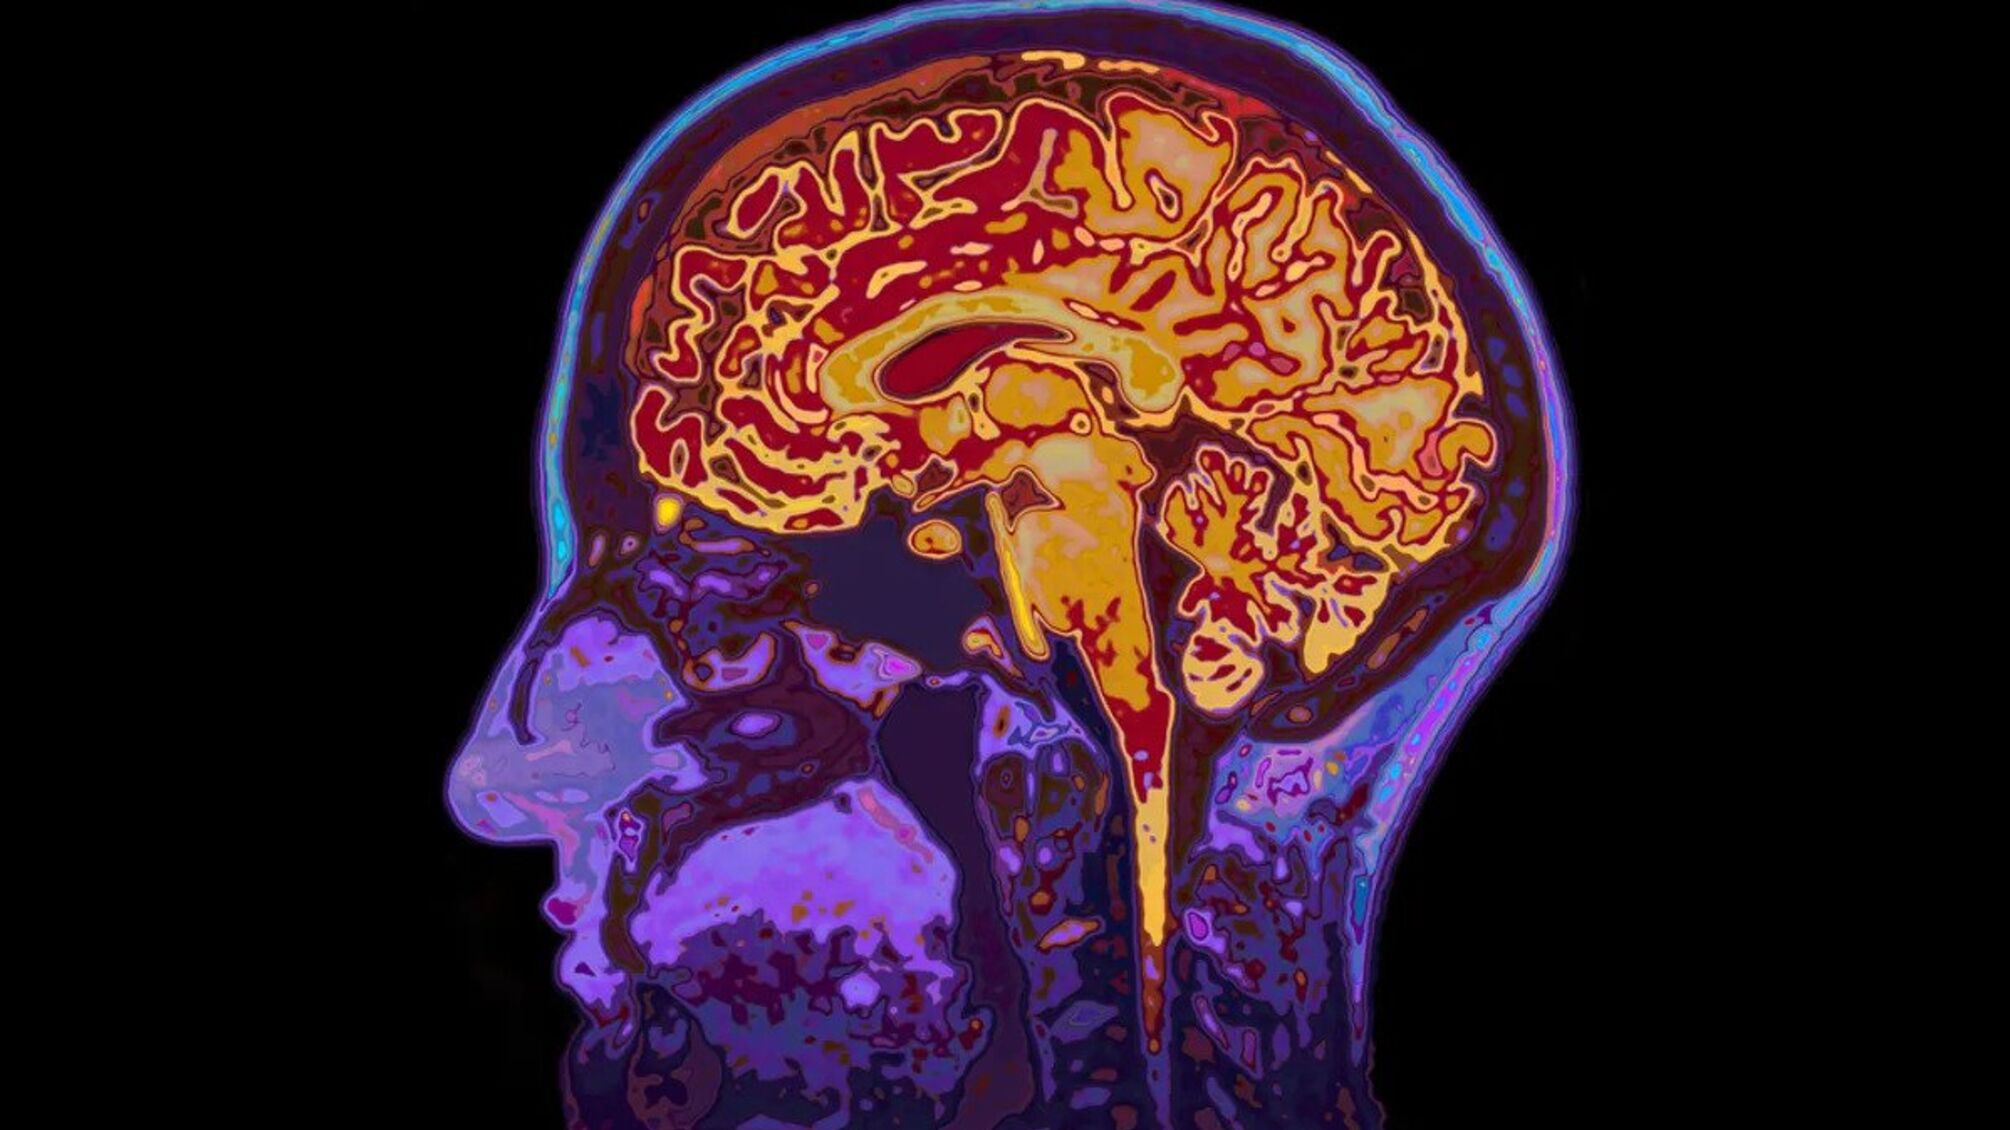

Исследователи проанализировали функциональные МРТ более 19 тысяч человек, отслеживая, как меняется активность разных участков мозга с возрастом. Они также изучали молекулярные изменения, в частности, какие гены активируются и какие биомаркеры сигнализируют о нарушениях.

Чтобы проверить эффективность, ученые провели клиническое исследование с участием 101 человека всех возрастов. Одной группе давали кетоны, другой — глюкозу, а затем проводили МРТ мозга.